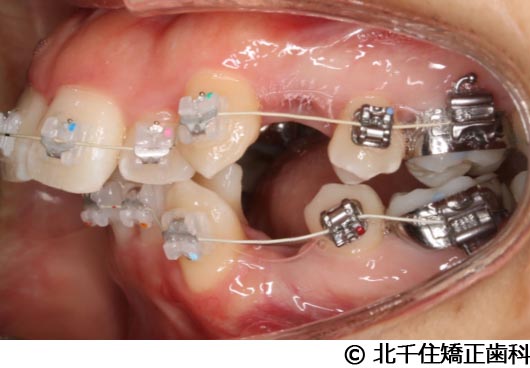

【症例1】顎関節症1

- 治療前

- 治療中

- 治療後

- 治療名

- 顎関節症1

- 費用

- 1,502,000円(税込)

- 期間

- 2年11ヵ月

- 治療回数

- 36回

- 通院頻度

- 1ヵ月ごと

- 年齢・性別

- 24歳9ヵ月・女性(初診時)

治療内容

-

患者様の症状

主訴:顎の左側偏位、前歯部叢生、出っ歯

治療方法

顎関節症(非復位性顎関節円板障害)、スタビライゼーションスプリントにより顎関節の安定化を図り、上下顎小臼歯4本を抜歯して矯正用アンカースクリューを併用してワイヤー矯正治療(セラミックブラケット)。

治療結果

スプリント療法後に顎位の安定化を図り、矯正治療により歯列および咬合関係の調整を行った症例である。現在は保定装置を使用し、歯列および咬合の安定維持のため定期的な経過観察を行っている。

※治療結果は個人差があります。

治療を行う上での注意点(リスク・副作用)

歯磨き不良に伴うカリエスや歯周病、顎関節症、歯根吸収など。